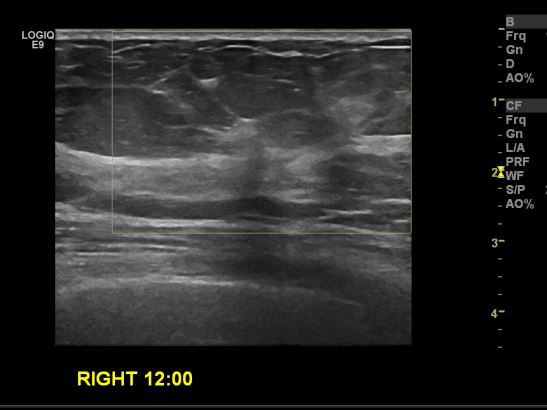

상기환자 건강검진상 이상 소견으로 내원하신 50대 여성 분으로 우측 12시 방향 타원 조직검사상 비정형 세포 발견되어 정밀 검진 위해 본원 조직검사 재 시행후 우측 침윤성 유관암 진단 되었습니다.